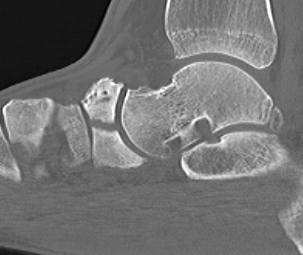

Imaging

Acute, minimally displaced navicular fracture

Acute displaced navicular fracture